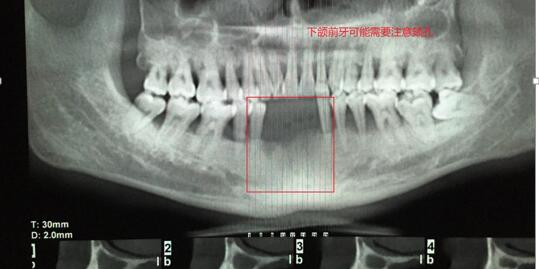

案例一:下頜磨牙缺失(非游離端)

吳X,女,46歲;主訴: 左下后牙缺失3月余,影響美觀?,F(xiàn)病史:左下后牙3個(gè)月前因牙體治療失敗在我院頜面外科拔除,現(xiàn)要求種植修復(fù)。既往史:否認(rèn)系統(tǒng)病史。檢查:36缺失,拔牙創(chuàng)愈合良好,缺失間隙近遠(yuǎn)中寬度7mm,頜齦距離正常,頰舌向?qū)挾燃s8mm。輔查:口腔CBCT顯示36可用牙槽骨高度(牙槽嵴頂?shù)较骂M神經(jīng)管)約18-19mm,頰舌側(cè)寬度12mm,骨質(zhì)正常,無(wú)疏松影像,鄰牙根尖周無(wú)暗影。 診斷: 36牙列缺損。治療計(jì)劃:種植義齒修復(fù)36牙列缺損。 處理: 1. 與患者說(shuō)明種植牙修復(fù)的治療過(guò)程,注意事項(xiàng)和費(fèi)用,患者同意種植修復(fù)。 2. 血常規(guī)檢查,全口牙潔治。 3. 患者口內(nèi)藻酸鹽...